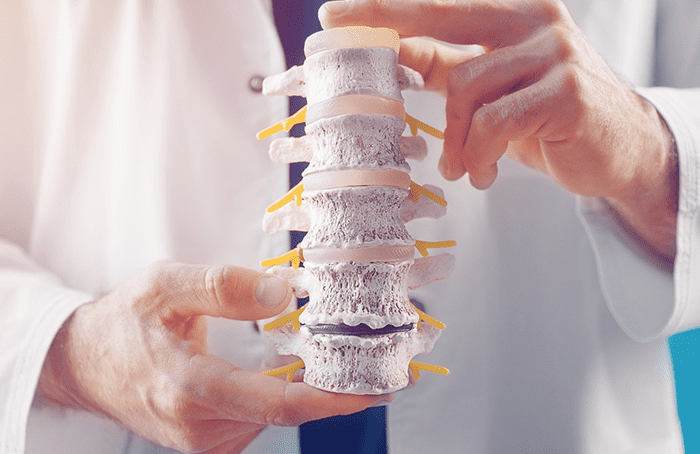

Manejo de osteoporosis

El manejo de la osteoporosis implica medidas preventivas como dieta y ejercicio, junto con medicamentos para fortalecer los huesos y reducir el riesgo de fracturas.